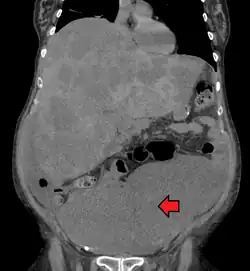

| Location and appearance of two example colorectal tumors | |